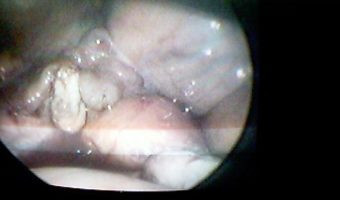

Vista laporoscópica de vesícula